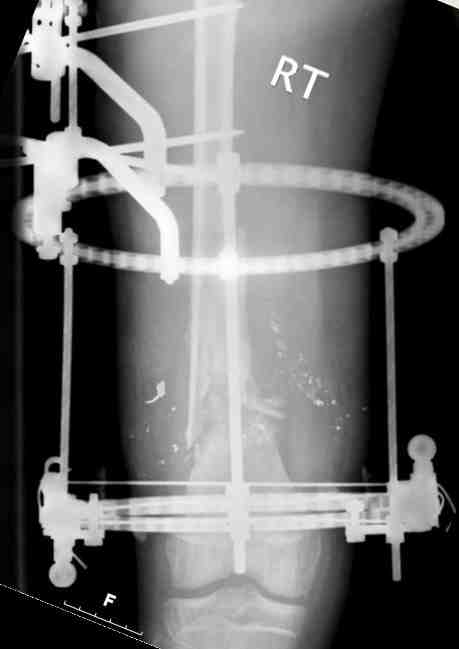

Выше приведены рентгенограммы 13-летнего подростка, страдающего от огнестрельного многооскольчатого перелома дистальной трети бедра. AO наружный фиксатор наложенный в день травмы не дал приемлемой редукции. Через три недели после перелома аппарат Илизарова был наложен без попытки одномоментной репозиции на операционном столе. There are X-Rays of a thirteen year old boy with a comminuted distal femur fracture secondary to a gunshot wound, initially treated with an AO external fixator. The alignment was unacceptable and an Ilizarov external fixator was applied three weeks after the injury. No attempt of definitive reduction was made during the surgery.

Гексаподная приставки наложена на 10 дней и приемлемая редукция была получена. The Hexapod set was applied for ten days and acceptable reduction was received.

По окончанию редукции Гексаподный сет был снят и дальнейшее ведение больного проходило в стандартном режиме аппарата Илизарова. Хороший анатомо-функциональный результат был получен. When reduction was finished, the Hexapod set was removed and further management has been continued by standard Ilizarov regime. Good anatomic and functional results were achieved.